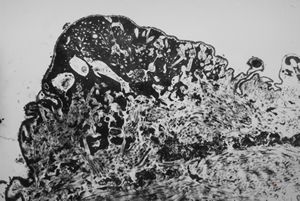

F,49y. | purulent meningitis- meningococcal v.s.